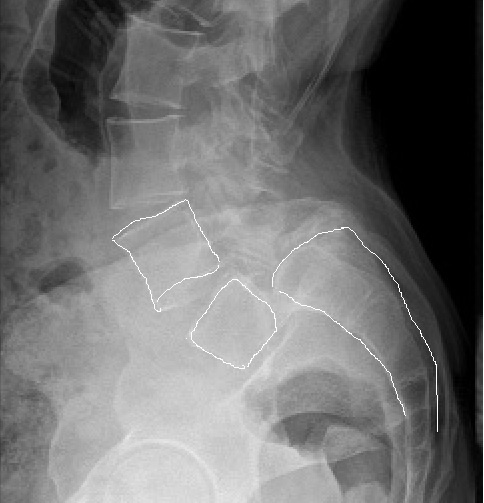

Не листез, а листезише!!!! Полное сползание позвонка L5 по крестцу!